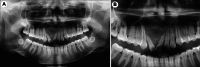

Myoepithelioma is a benign salivary gland tumor. Central myoepitheliomas are very rare. The aim of this report was to describe a case of maxillary myoepithelioma. A 14-year-old female patient presented with an multilocular lesion in the anterior maxilla, with nearly 8 months of duration. The lesion was asymptomatic, and the patient's dental history was unremarkable. The diagnostic hypothesis was an odontogenic tumor. Biopsy specimen consisted of nests of plasmacytoid cells in a myxoid stroma without duct formation. No cellular atypia or bone and cartilage formation were noted. The neoplastic cells were positive for Pan-cytokeratin, S100, CK7, and CK8. The final diagnosis was myoepithelioma. The patient was treated by surgical excision followed by bone curettage, and no signs of recurrence were found after 8 years of treatment.